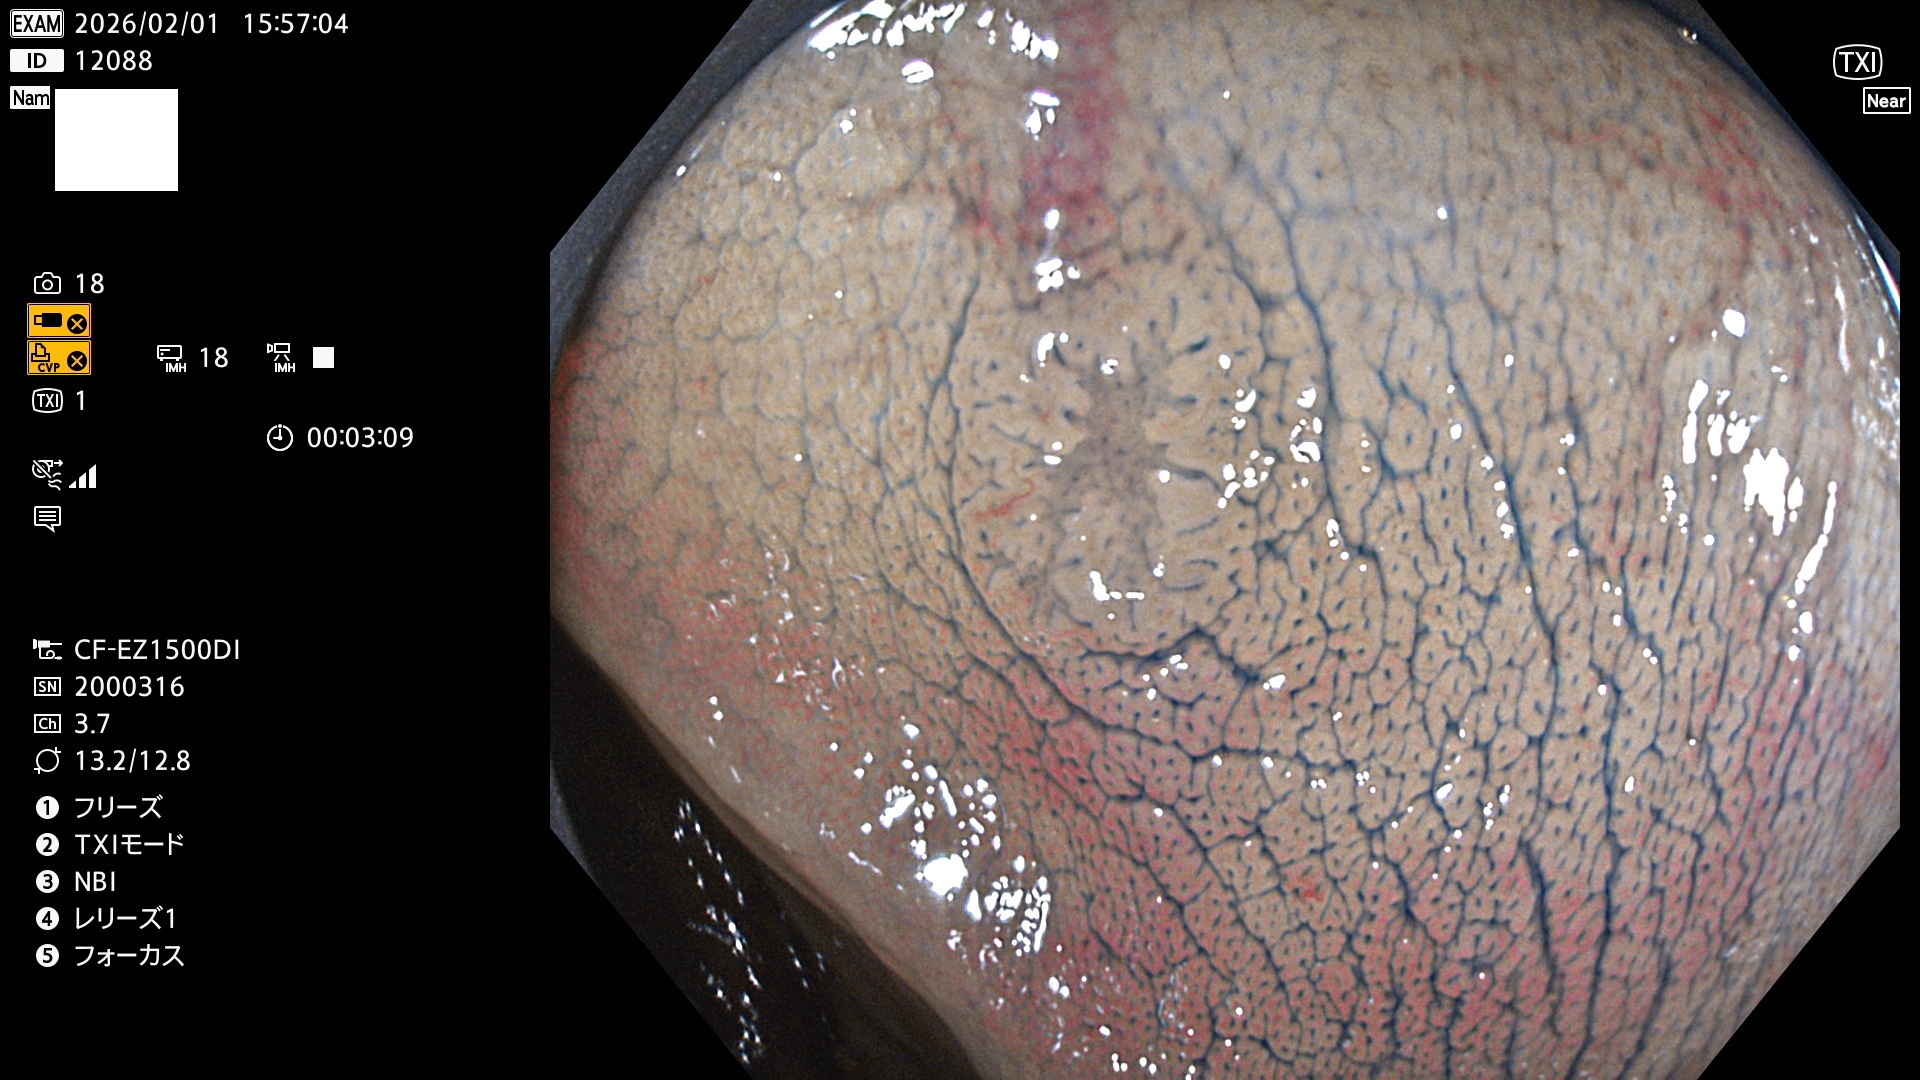

完全に平坦な物をUb、陥凹している物をUcと呼びます。Ubは認識が困難で、Ucはびらん(炎症)と紛らわしいために見落とされやすく、「内視鏡後・大腸癌」の原因になります。

専門的)Uc=De Novo癌? 内視鏡の解像度が低かった時代、このような説もありました。しかし今日の高精度内視鏡では良性の微小なUc型腺腫(APC遺伝子異常の腺腫)が日常的に見つかります。Ucこそが多段階発癌(Adenoma-Carcinoma Sequence)のMain Routeです。

毎週の検査(木・金・土・日)に発見されたUbとUc型・腺腫を、その週の日曜の夜にUPし1週間、提示します。

2026年1月29日〜2月1日の4日間(40件)10個 (Uc_ADR=10個/40人=25%)